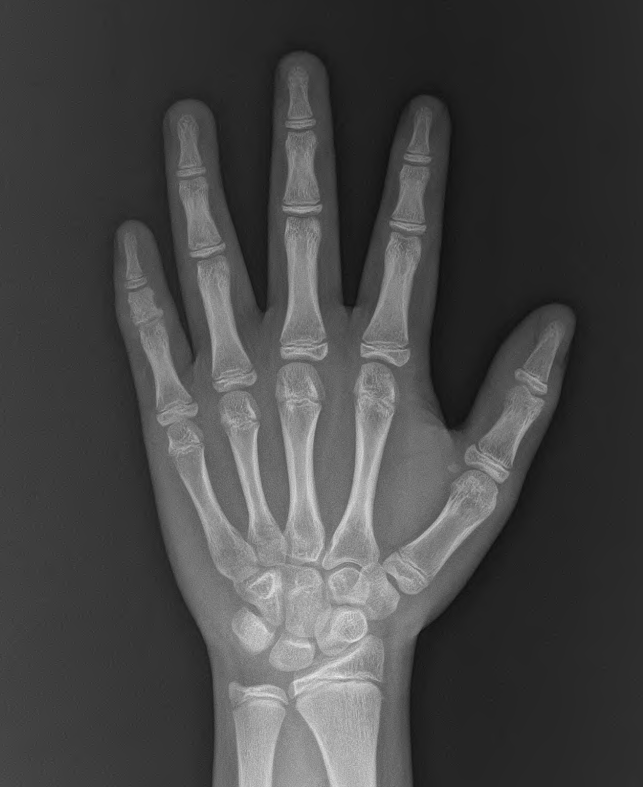

뼈나이는 어떨까요?

qqr.png

qr.png

실제 나이보다 1년 정도 앞서가고 있습니다. 처음 성조숙증 억제주사를 시작하기 전 2년 정도 앞서가 있던 것을 생각하면, 어느 정도 잘 조절된 것을 알 수 있습니다.